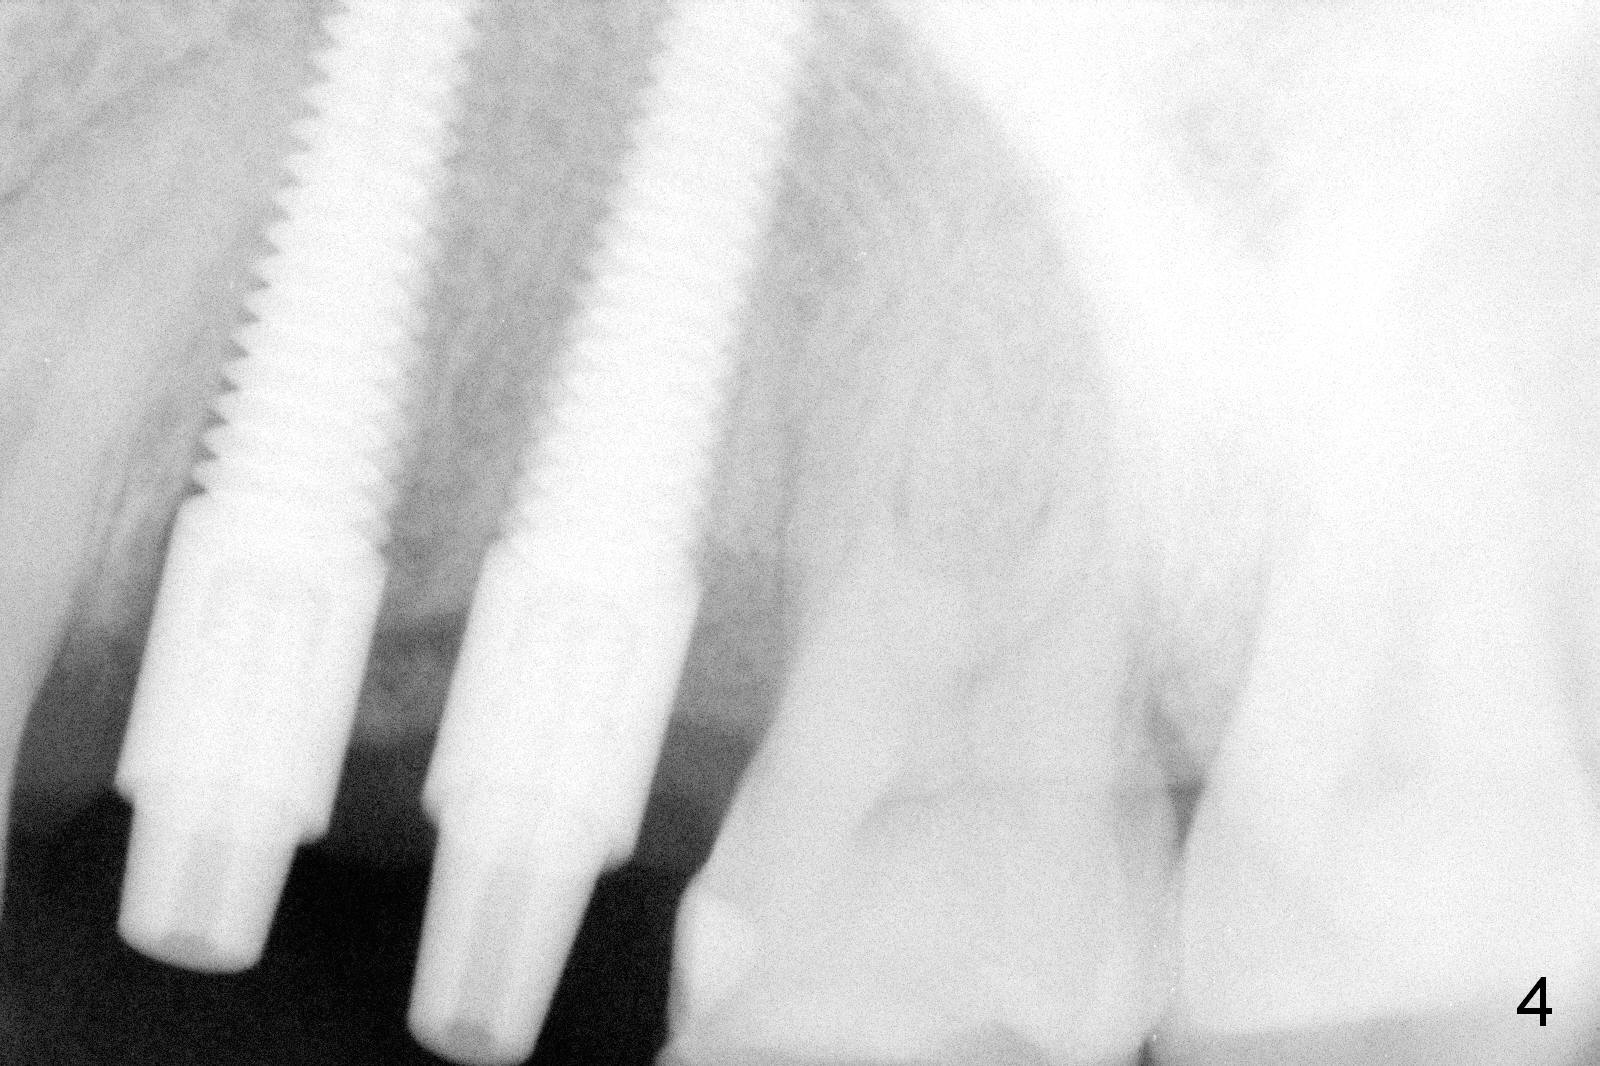

Taking 2 additional PAs with sensor 1 is frustrating (Fig.1,2), no apices shown. Osteotomy is done smoothly with 2 mm pilot drill at 20 mm, 2.5 mm reamer at 17 mm, and 3 mm reamer at 14 mm and 4.5x20 mm tap at 17 mm. The 1st intraop PA is taken with sensor 1 when 2 of 4.5x20 mm implants are placed (Fig.3); the implant at #12 is close to the root of the tooth #11. The 2nd PA is taken with sensor 2: the apex of #11 touches the implant at #12 (Fig.4). There is no separation when panoramic X-ray is taken (Fig.5). Effort is exerted to re-direct the osteotomy twice (Fig.6: tap; Fig.7: implant) without success. When the implant is removed, a PA is taken; it appears that the root of the tooth #11 has no damage (Fig.8). To obtain the best recovery, socket preservation is carried out with 50/50 cortical/cancellous allograft mixed with Osteogen (Fig.12 *) and Collagen Dressing (Fig.9: #12). A 2 (or 3)-unit provisional bridge (Fig.10: #12,13) is fabricated over the implant (Fig.9 I)/abutment (A) to cover these 2 sockets. After acid etching #11 D surface (Fig.9 >) and relining (Fig.11 *), the provisional bridge is bonded to the tooth #11 (Fig.11,12 black >) so that bone graft will be less likely dislodged.